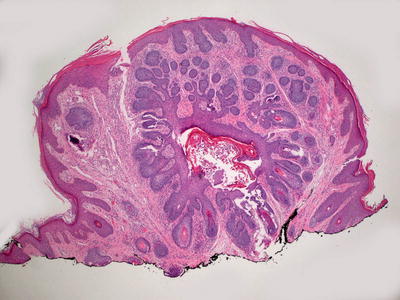

Fig. 24.2

Pilomatricoma demonstrates a sharply circumscribed dermal tumor consisting of basaloid cells at the periphery, ghost cells and a keratinaceous center